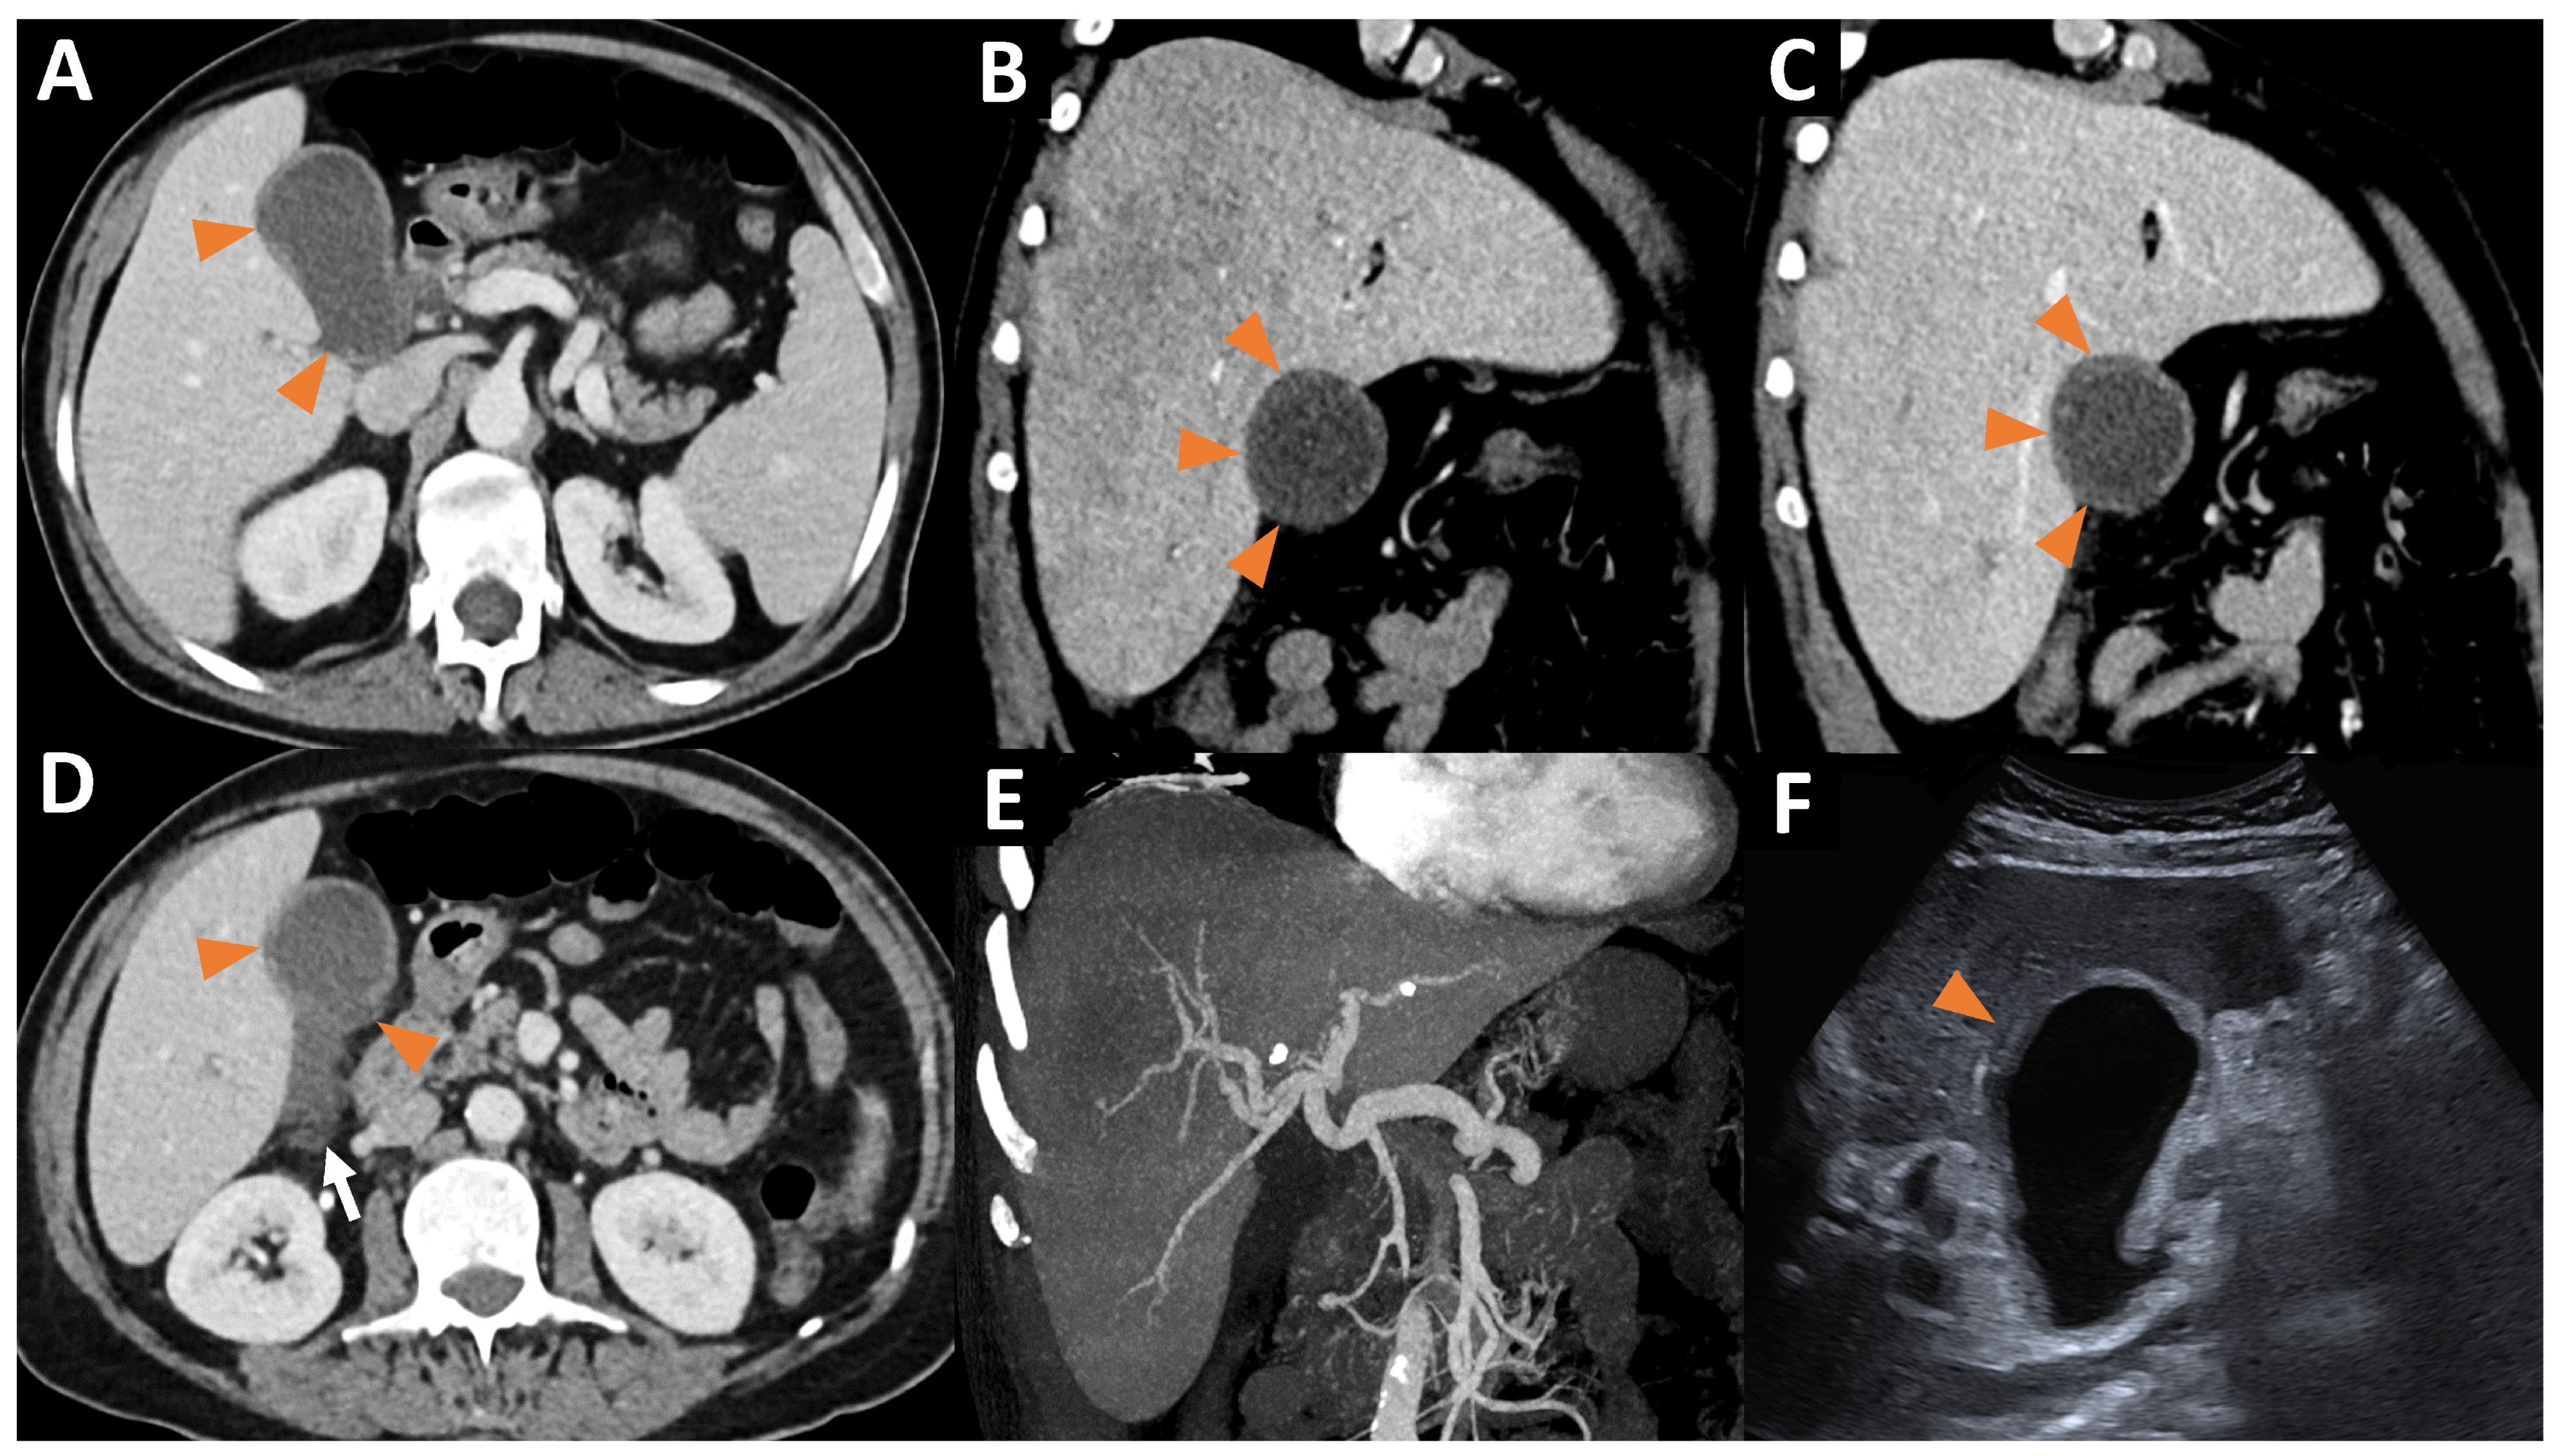

2. Case Presentation